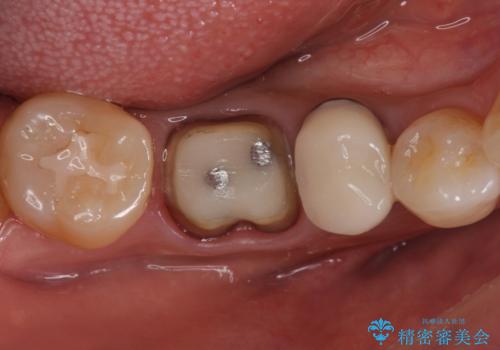

- 口を開けたときに下の歯の銀歯が目立つから白くしたいとのことで来院されました。

根管治療はご希望されなかったため、被せ物のみをやり替えていきます。

- 右下6 仮歯+ジルコニアクラウン 11,000円+121,000円費用は治療当時の料金となります